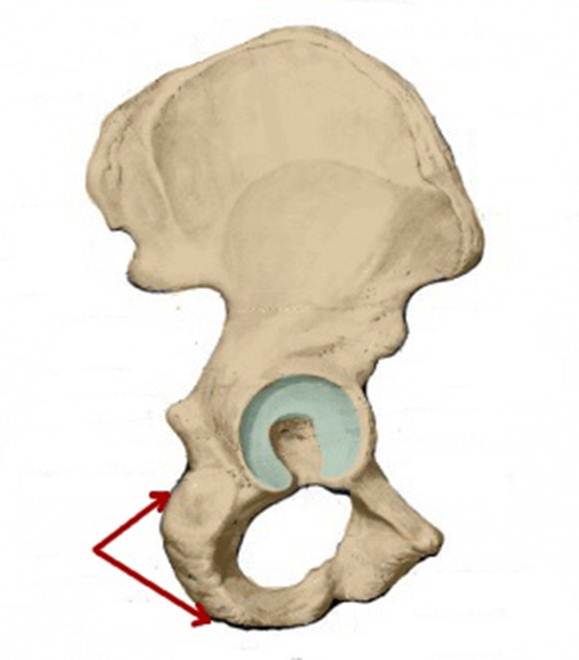

S: Стрелка указывает на tuber ischiadicum (латинский язык).

I:

S: Стрелка указывает на foramen obturatum (латинский язык).

I:

S: Стрелка указывает на sulcus obturatorius (латинский язык).

I:

S: Стрелка указывает на Conjugata vera

I:

S: Стрелка указывает на Conjugata diagonalis

I:

S: Стрелка указывает на lig. Sacrospinale

I:

S: Стрелка указывает на лобковый симфиз (русский язык).

I:

S: Стрелка указывает на art. sacroiliaca (латинский язык).

I:

S: Стрелка указывает на foramen ishiadicum majus

I:

S: Стрелка указывает на foramen ishiadicum minus

I:

S: Стрелка указывает на lig. Sacroiliaca posteriora

I:

S: Стрелка указывает на lig. Sacrococcygeum anterius

I:

S: Стрелка указывает на membrana obturatoria (латинский язык).